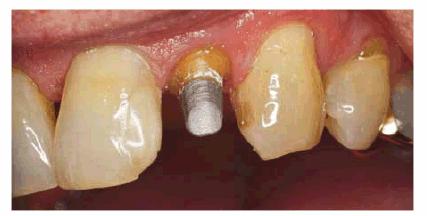

shallow, then a post should be used to provide retention for the core (Figur 323s1823d e 18-13A). Usually, only one post is needed.

A prefabricated post should be cemented into the largest canal. In mandibular

molars, this will typically be the distal canal. No attempt should be made to

place a post in the mesial canal of a mandibular molar as the distal wall of

the mesial root is thin and easily perforated. For maxillary molars, a single

post in the lingual canal is adequate. Because the direction of the post is

divergent from the pulp chamber, it creates excellent retention for the core (Figur 323s1823d es 18-13B 18-13C 18-13D 18-13E, and 18-13F

Figur 323s1823d e 18-13A: Prefabricated post with core.

Figur 323s1823d e 18-13B: Tooth #3 after successful root canal treatment.

Figur 323s1823d e 18-13C: Inadequate pulp chamber wall height and lack of remaining tooth structure evident after removal of previous restorative materials. Additional retention with prefabricated post is indicated.

Figur 323s1823d e 18-13D: Completed core build-up on tooth #3.

Figur 323s1823d e 18-13E: Completed crown preparation on tooth #3. Note that the preparation margin extends apical to the core-tooth interface.

Figur 323s1823d e 18-13F: Composite resin may also be used as core material.